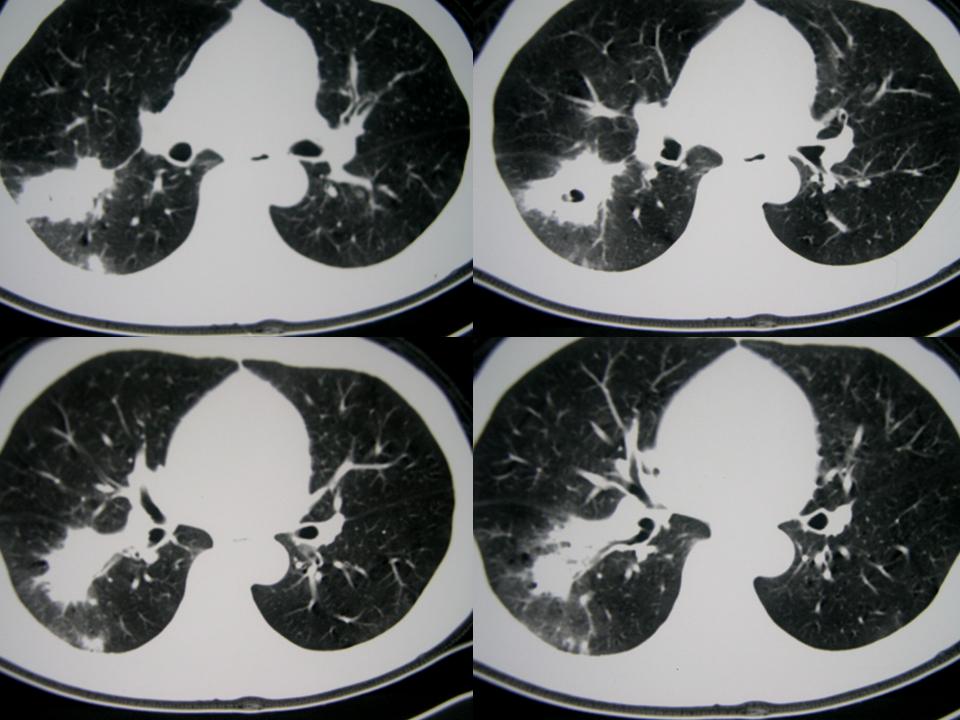

男性,65岁。主诉:干咳5年,加重月余。5年中多次发作,每次持续时间长短不一,静脉滴注缓解;近月余加重,用药效果差。晨起加重,痰少,无发热,无血丝

右肺下叶实质性肿块,边缘毛刺,内见偏心空洞。支持:周围性肺癌!

2、右下肺叶团片状影,见空泡征、分叶征、毛刺征及偏心性空洞,符合肺癌(腺癌可能性大)

应该是周围型肺癌!!!!浸润多个细支气管!

考虑右肺下叶周围型肺癌(癌性空洞形成)并阻塞性肺炎。